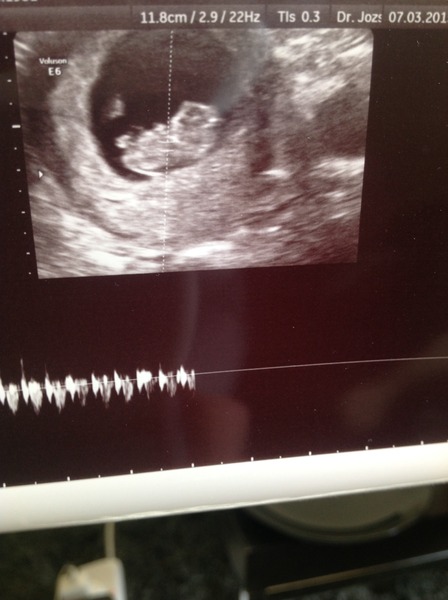

batfish · 07/03/2015 11:04

Well to those of you with no symptoms - it is absolutely nothing to worry about! Just saw my little 2.5cm long baby and all is fine, I am soooooo relieved! Thank you for putting up with my loony worrying Smile

Pictures bat!

Yay batfish great to hear. Think we need pics of bean.

batfish · 07/03/2015 12:16

Here is baby bat!

AuntieDee · 07/03/2015 12:18

I'm so pleased for you! That's absolutely lovely xx

I'm really annoyed with my scan as they wouldn't let me have a pic, even taken with my phone camera :(